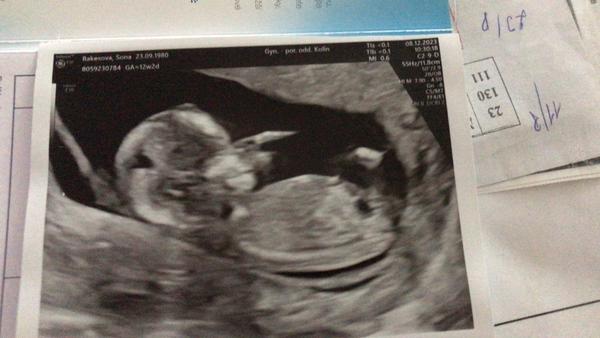

Tipnete si pohlaví z obrázku? Holka nebo kluk?

Ahojte, na 1. screeningu nám nechtěl říct pohlaví, jen z principu že to neříká 😄 ale natočený byl pěkně, všechno nám ukázal. Zkusíte tipnout ? Jednu fotku máme zespod a jednu z boku přímo na pohlaví. My jsme mu svůj tip řekli ale na to nám jen odpověděl bez komentáře 😄🙈

Fotky jsou to teda strasny, nechapu, že dneska ještě někdo používá tahle starý stoje🙄